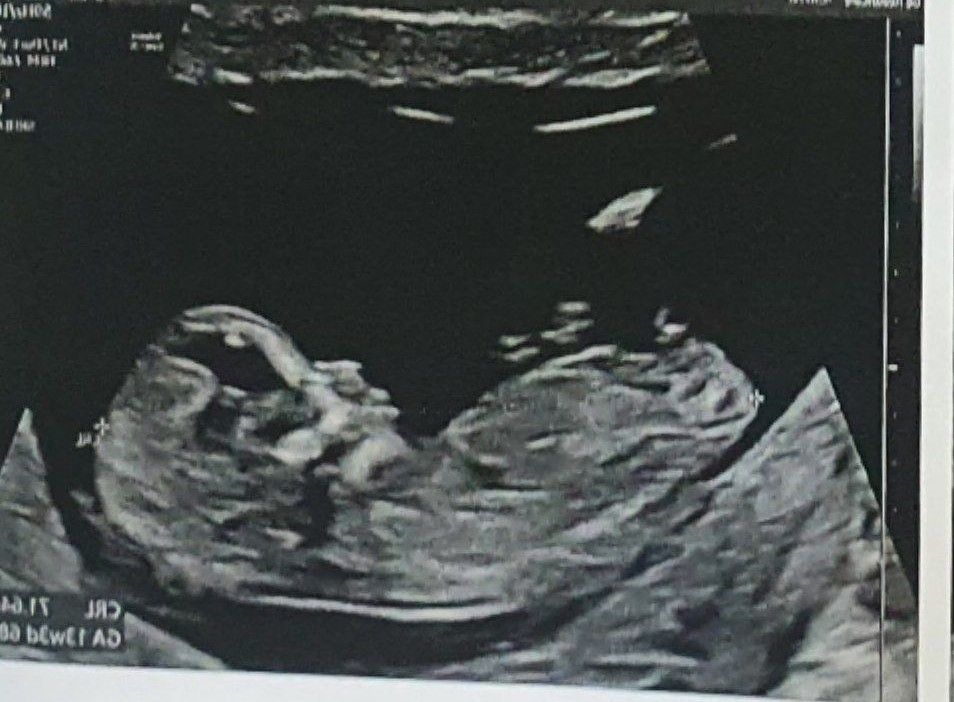

1 скрининг прошел хорошо, записалась на 2й на 20 января.

Недели с 15 начала ощущать изредка побулькивания внутри, как это и было с первым сыном. В 16 недель был впервые ощутимый пиночек. Сегодня 16+2 и эти пару дней сын толкается пару раз вечером в одно и то же место.